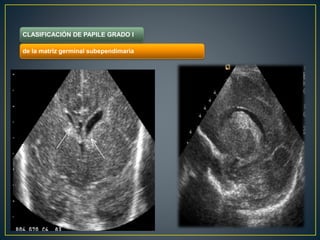

CLASIFICACIÓN DE PAPILE GRADO I

de la matriz germinal subependimaria

. CLASIFICACIÓN DE PAPILEGRADO I de la matriz germinal subependimaria